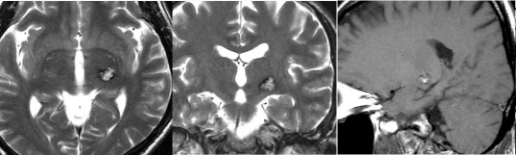

18岁的多发脑海绵状血管瘤患者嘉佳,4岁时在国内进行了一开始手术,切除了两侧的海绵状血管瘤。多年来反复出血,再次手术还会复发吗?

巴教授回复

“如果我们决定手术,手术切除率将达到全切。完全切除后,复发的可能性较低,但在海绵状血管瘤中,答案不是全切,因为这是一种遗传性疾病。由于基因的驱动,在另一个地方,现在看不见的新病变可能会在后期发生(这不是必然的,但有可能)。”